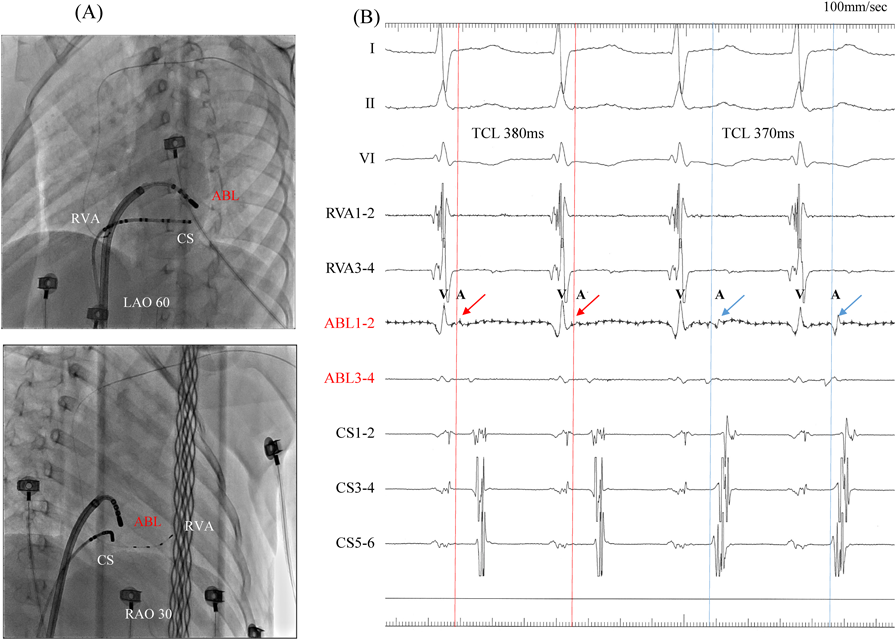

Fig. 6 Fluoroscopic images and intracardiac electrocardiogram during the second atrioventricular reciprocating tachycardia (AVRT). (A) Upper panel: the left anterior oblique (LAO) view. Lower panel: the right anterior oblique (RAO) view. The ablation catheter is positioned at the site of successful ablation. (B) The left anterolateral accessory pathway was interrupted with a radiofrequency application, and different supraventricular tachycardia, which was long RP tachycardia, appeared spontaneously.

ABL, ablation catheter; CS, coronary sinus electrode; HBE, His bundle electrogram; LA, left atrium; LV, left ventricle; RVA, right ventricular apex electrode; TCL, tachycardia cycle length.